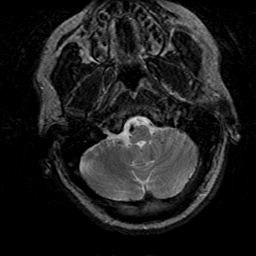

Subacute Stroke, overlay -- Slice #3

[Home][Help][Clinical] Slice 3